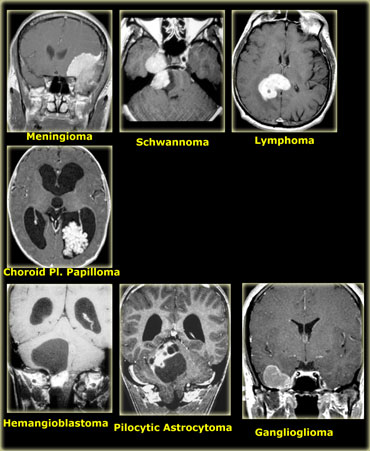

Incidence of CNS tumors

Roughly one-third of CNS tumors are metastatic lesions, one third are gliomas and one-third is of non-glial origin.

Glioma is a non-specific term indicating that the tumor originates from glial cells like astrocytes, oligodendrocytes, ependymal and choroid plexus cells.

Astrocytoma is the most common glioma and can be subdivided into the low-grade pilocytic type, the intermediate anaplastic type and the high grade malignant glioblastoma multiforme (GBM).

GBM is the most common type (50% of all astrocytomas).

The non-glial cel tumors are a large heterogenous group of tumors of which meningioma is the most common.